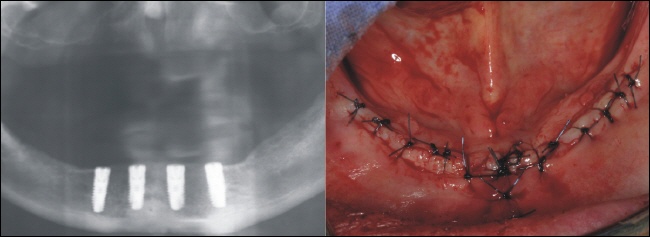

![]() |